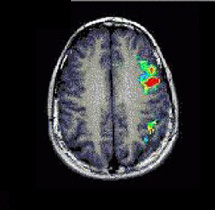

Case 3

| Patient | Male patient, age 14, with seizures |

| Paradigm | Tapping task ON: Alternating Finger Tapping with the right hand OFF: Think of nothing |

| Results | Cortex of the left central sulcus was strongly activated. The relation to the tumor is clearly depicted by the images. |

| Comments | The tumor was resected without postoperatory motor deficit |